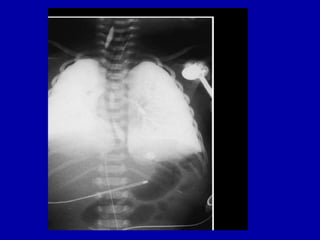

X-ray - RDS

RDS

43

44